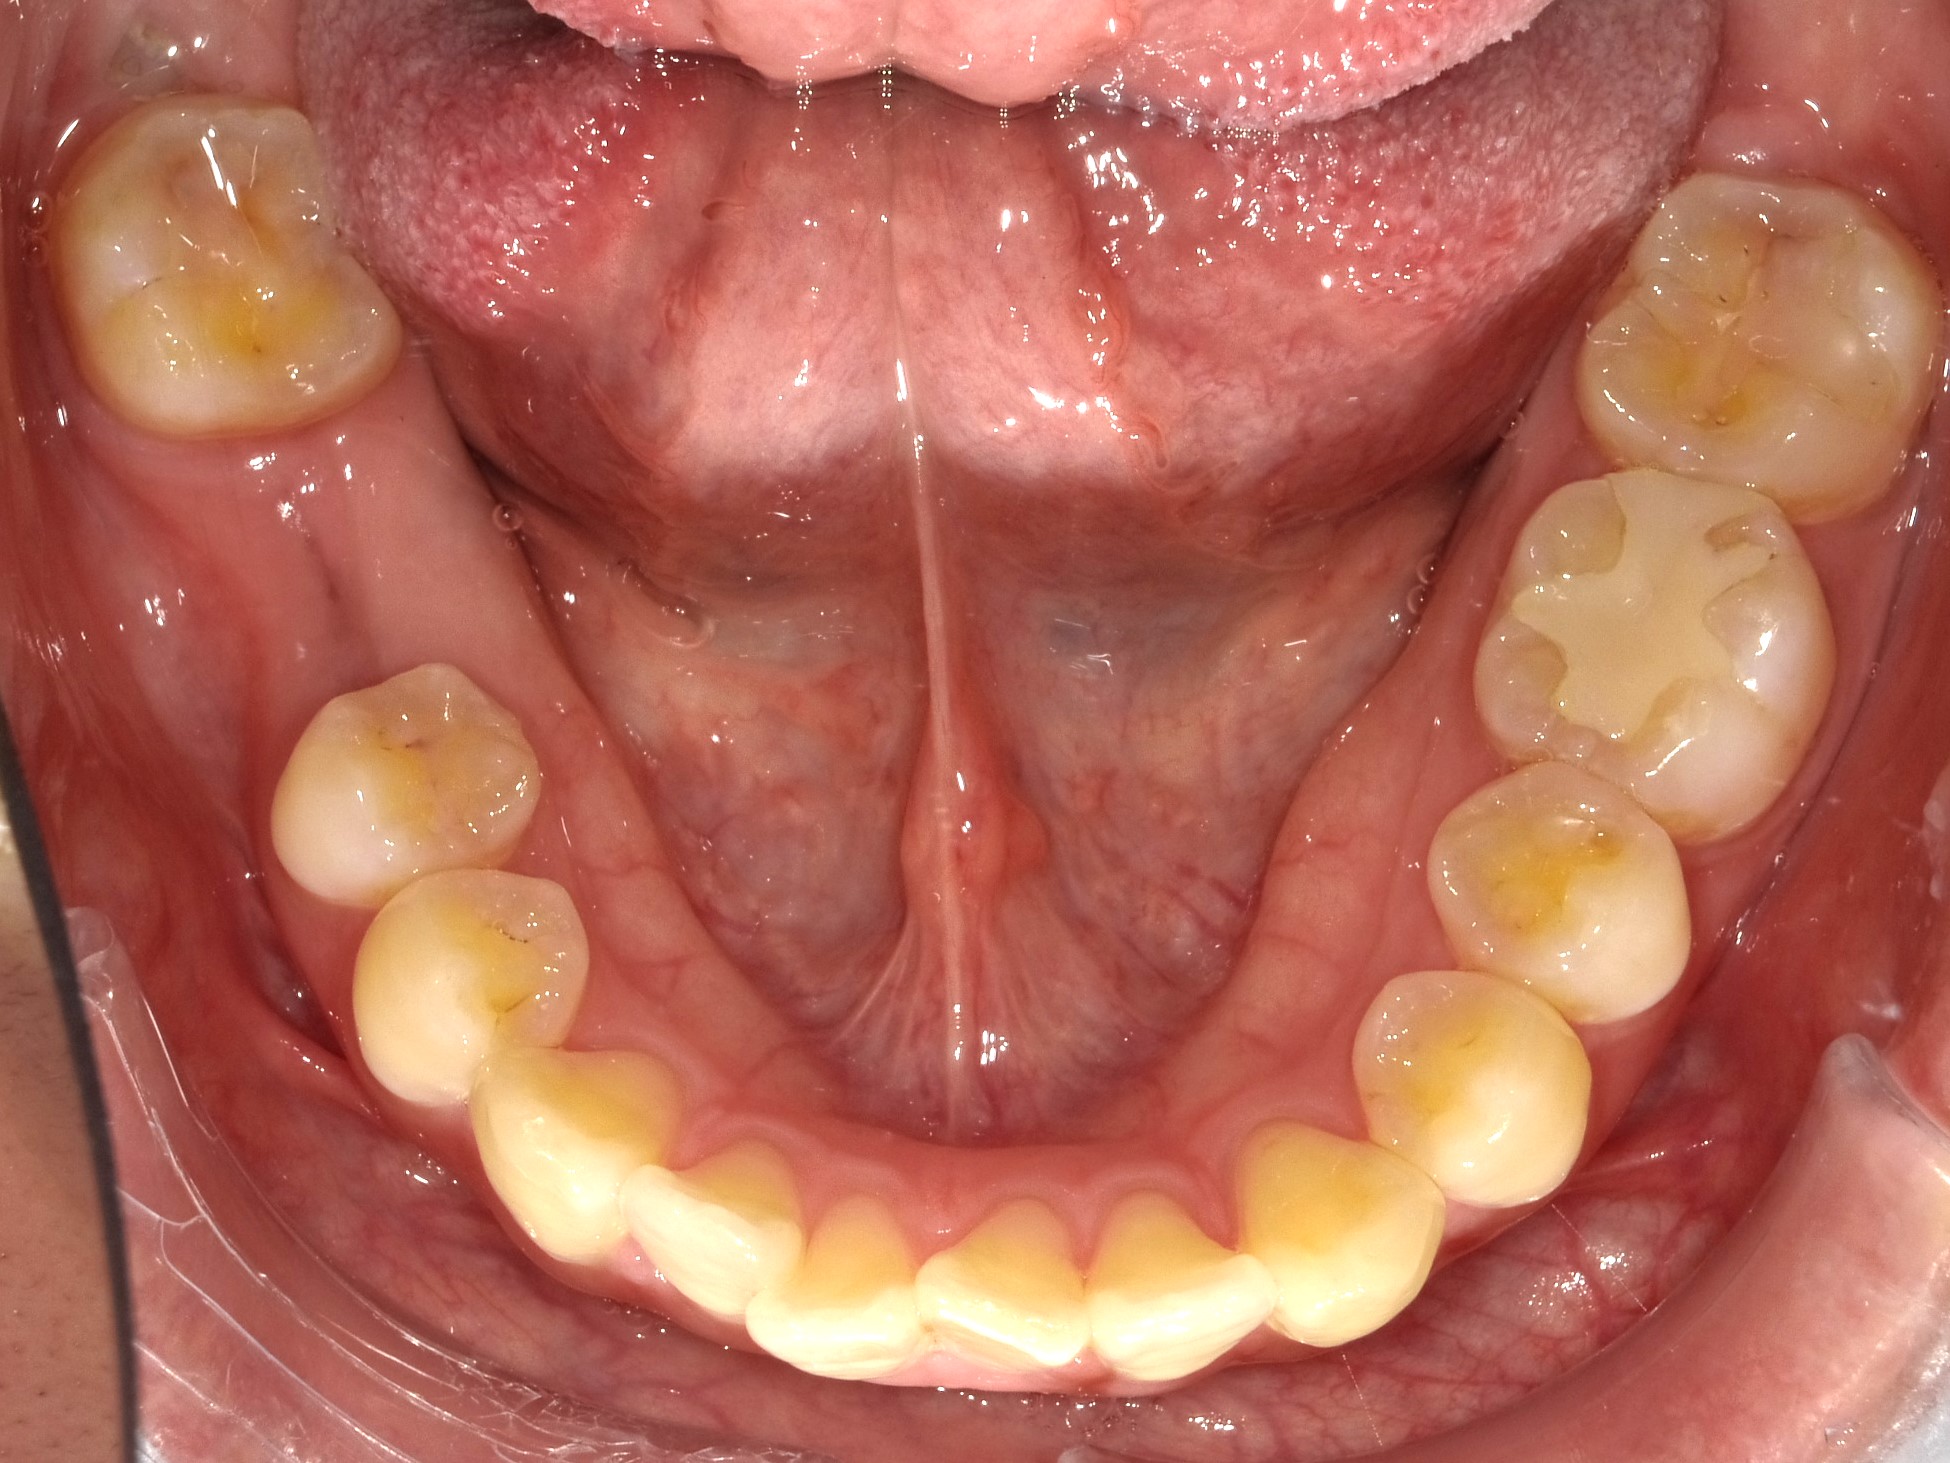

治療後

| 年齢・性別 | 30代・女性 |

| 主訴 | 右下6番むし歯にて状態悪く抜歯後、部分入れ歯を使用したが、違和感が強く使用不可の為、インプラント希望 |

| 期間 | 6か月 |

| 費用 | 552,850円 |